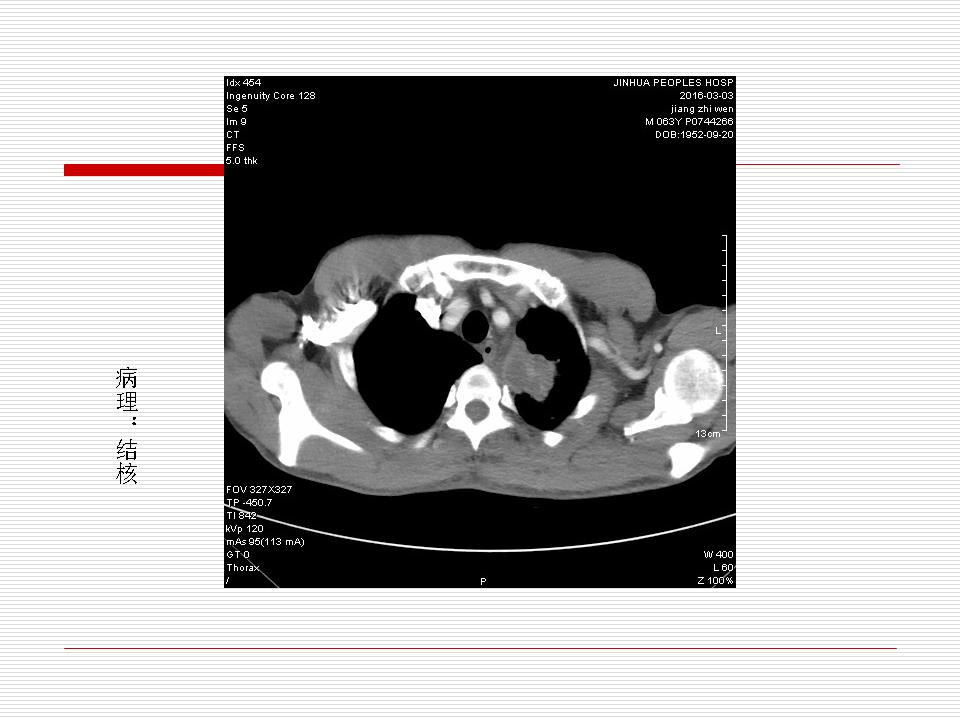

肺部阴影永恒且最重需要鉴别的是:到底是炎症还是肿瘤?但临床的病例中的影像表现难以界定或有些肿瘤特征,同时又有些炎症特点是非常常见的情况。作为临床医生我们怎么去总结分析,并找到之所以是炎症或之所以是肿瘤的细微差别或特点非常重要,也非常有用。2019.12.7浙江省2019年胸心外科学学术年会在宁波召开时,我的临床病例分析与经验总结<那些像肺癌的炎症与像炎症的肺癌>获得在大会交流的机会,以下为该PPT的内容,与你分享,希望对同道有益,有借鉴与启迪。若有探讨与进一不完善的建议,欢迎文末留言讨论: